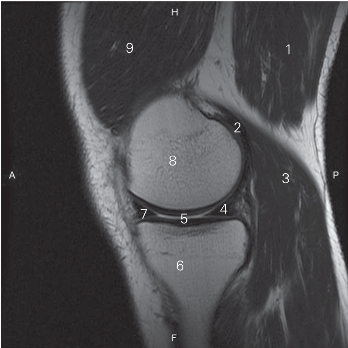

图5-25 经股骨内髁的矢状断层MR T1加权图像

1 半膜肌 semimembranosus

2 腓肠肌肌腱内侧头 gastrocnemius medial head tendon

3 腓肠肌内侧头 medial head of gastrocnemius

4 内侧半月板后角 posterior horn of medial meniscus

5 关节腔 articular cavity

6 胫骨 tibia

7 内侧半月板前角 anterior horn of medial meniscus

8 股骨内侧髁 medial condyle of femur

9 股内侧肌 vastus medialis